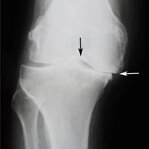

L'osteoartrite distrugge progressivamente il tessuto cartilagineo e porta alla deformazione dell'articolazione. Col tempo, anche i movimenti più semplici diventano impossibili e il dolore diventa costante. Una terapia adeguata aiuta a fermare la progressione della malattia.

Gonfiore e infiammazione dell'articolazione del ginocchio sono un segnale d'allarme di gravi patologie. Senza trattamento, possono portare alla completa perdita di mobilità e alla necessità di un intervento chirurgico. Agisci immediatamente ai primi sintomi!